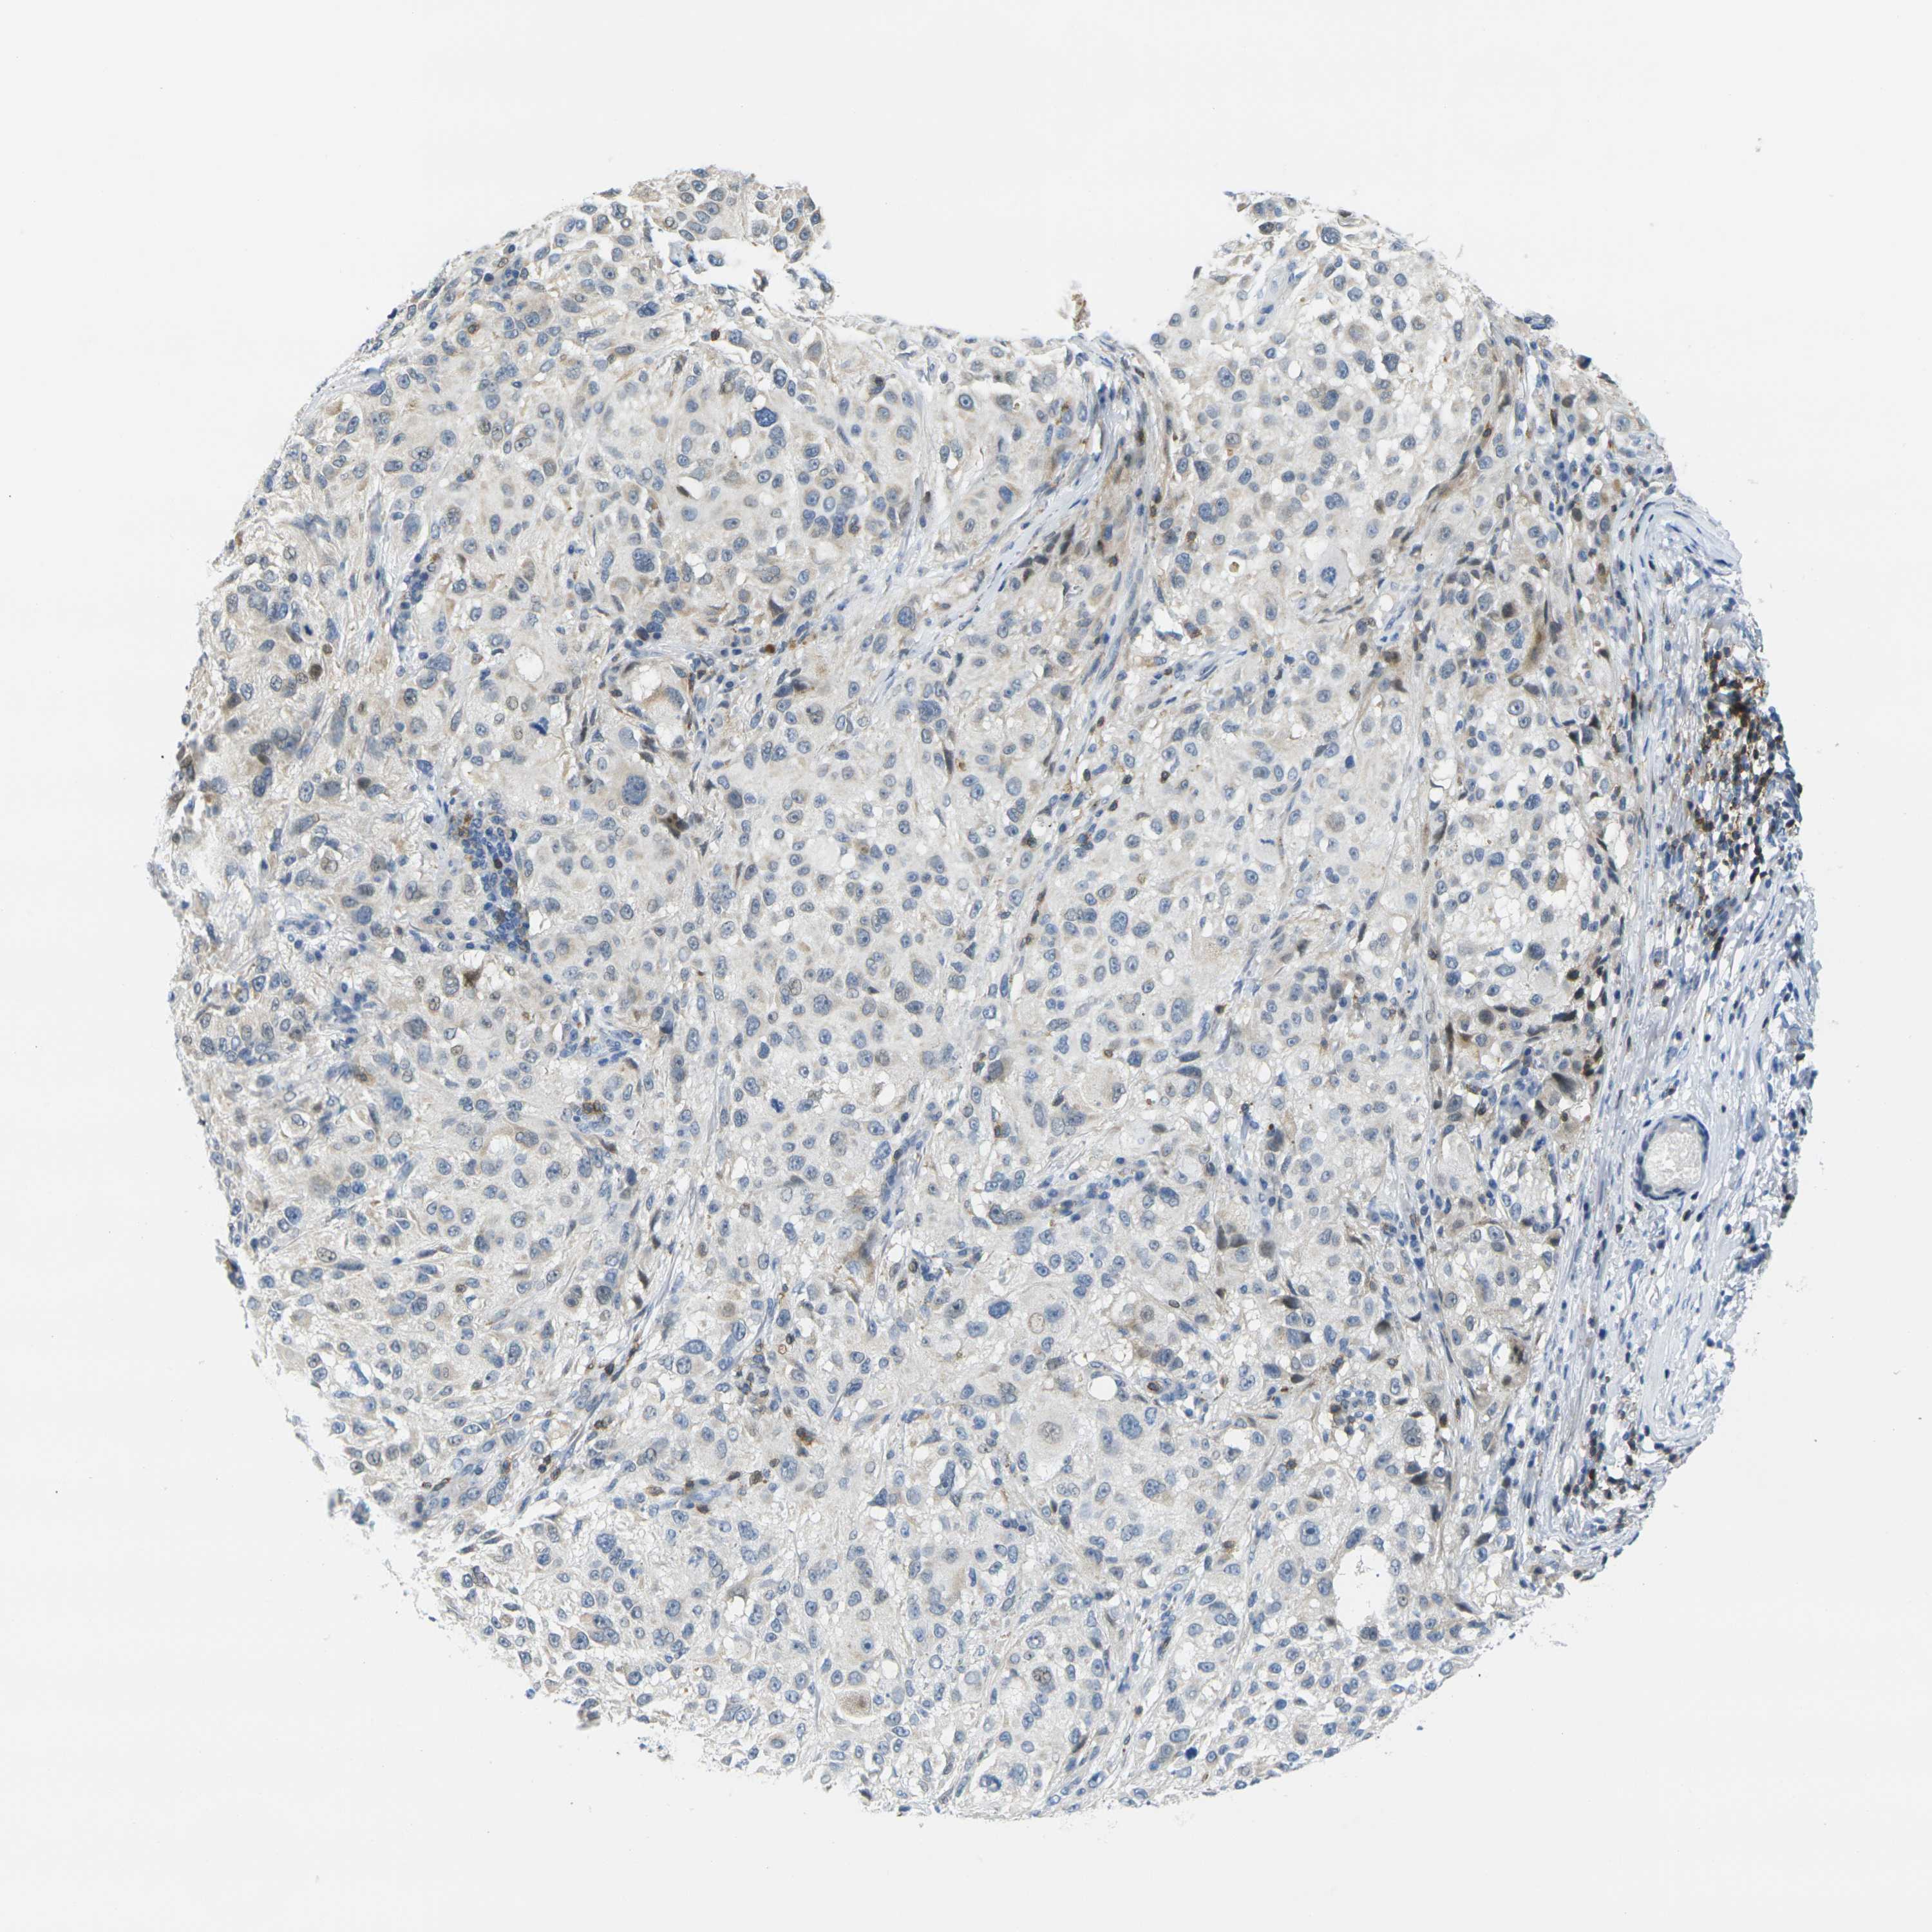

MELANOMA - Protein expressioni

A mouse-over function shows sample information and annotation data. Click on an image to view it in a full screen mode. Samples can be filtered based on level of antibody staining by selecting one or several of the following categories: high, medium, low and not detected. The assay and annotation is described here.

Note that samples used for immunohistochemistry by the Human Protein Atlas do not correspond to samples in the TCGA dataset.

Antibody stainingi

Antibody staining in the annotated cell types in the current human tissue is reported as not detected, low, medium, or high, based on conventional immunohistochemistry profiling in selected tissues. This score is based on the combination of the staining intensity and fraction of stained cells.

Each image is clickable and will lead to virtual microscopy that enables deeper exploration of all samples and also displays staining intensity scores, fraction scores and subcellular localization as well as patient and tissue information for each sample.

Antibody HPA071778

Antibody CAB013055

Malignant melanoma, NOS

Malignant melanoma, Metastatic site

Malignant melanoma in situ